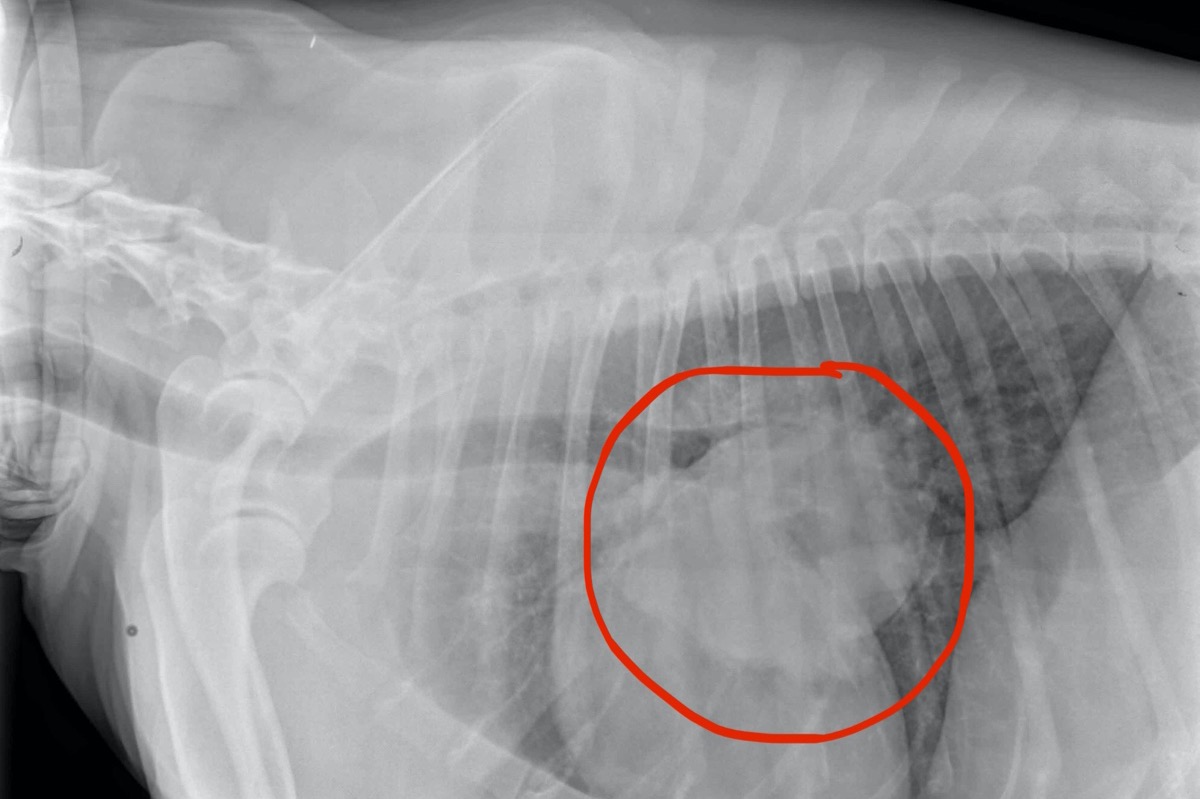

Hello! My name is Jake, I'm a 5 1/2 year old ESA certified black lab and on January 11th I was diagnosed with cancer. After my owner, Kate noticed I was having difficulty breathing the vet found a large tumor in my chest. In my defense I was just trying to grow a second heart because I have so much love to give.

The good news is that after Kate took me to a doggy oncologist this tumor is operable! and with my age there is a good prognosis of recovery! The bad news is the estimated vet bill for a CT scan (required), lobectomy, sending a sample to pathology and recovery is $11,931. I have been with Kate since she rescued me from a shelter in 2017 and certified me to be an emotional support animal. My owner has worked hard to overcome PTSD and I don't want to brag but I know I have been a huge help to my human, keeping her active, happy and keeping her company though the good times and hard times. Last summer Kate and I drove all the way from Oregon to New York because Kate is going to Physician Assistant School.

The good news is that after Kate took me to a doggy oncologist this tumor is operable! and with my age there is a good prognosis of recovery! The bad news is the estimated vet bill for a CT scan (required), lobectomy, sending a sample to pathology and recovery is $11,931. I have been with Kate since she rescued me from a shelter in 2017 and certified me to be an emotional support animal. My owner has worked hard to overcome PTSD and I don't want to brag but I know I have been a huge help to my human, keeping her active, happy and keeping her company though the good times and hard times. Last summer Kate and I drove all the way from Oregon to New York because Kate is going to Physician Assistant School.

The good news is that after Kate took me to a doggy oncologist this tumor is operable! and with my age there is a good prognosis of recovery! The bad news is the estimated vet bill for a CT scan (required), lobectomy, sending a sample to pathology and recovery is $11,931. I have been with Kate since she rescued me from a shelter in 2017 and certified me to be an emotional support animal. My owner has worked hard to overcome PTSD and I don't want to brag but I know I have been a huge help to my human, keeping her active, happy and keeping her company though the good times and hard times. Last summer Kate and I drove all the way from Oregon to New York because Kate is going to Physician Assistant School.

The good news is that after Kate took me to a doggy oncologist this tumor is operable! and with my age there is a good prognosis of recovery! The bad news is the estimated vet bill for a CT scan (required), lobectomy, sending a sample to pathology and recovery is $11,931. I have been with Kate since she rescued me from a shelter in 2017 and certified me to be an emotional support animal. My owner has worked hard to overcome PTSD and I don't want to brag but I know I have been a huge help to my human, keeping her active, happy and keeping her company though the good times and hard times. Last summer Kate and I drove all the way from Oregon to New York because Kate is going to Physician Assistant School.  Kate's exposure to healthcare left her with a profound appreciation for those that provide healing to patients and she knew she had to pay it forward. Now enrolled in Stony Brook's PA class of 2022, Kate primarily relies on loans and financial aid to make ends meet...and my tumor was not in the budget. I am so thankful my owner is choosing to fight for me and get the care I need. Please consider joining Kate in this journey and fund Jake's fight against cancer!